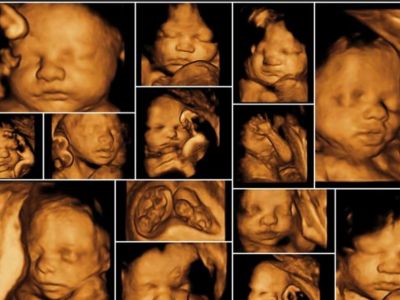

3D/4D Anomaly Scan

Raaya Diagnostic Center offers advanced 3D/4D anomaly scan services for expectant mothers, providing detailed and immersive views of fetal anatomy between 18 to 22 weeks of pregnancy. This specialized ultrasound examination not only assesses fetal development and anatomy for any abnormalities but also offers the unique opportunity for parents to see their baby’s features in three-dimensional and real-time imaging.

With our state-of-the-art 3D/4D ultrasound technology and experienced sonographers, Raaya Diagnostic Center ensures comprehensive and accurate evaluations during the anomaly scan. Our compassionate team provides support and guidance to expectant parents, creating a memorable and reassuring experience as they bond with their unborn child. Contact us to schedule your appointment or to learn more about our obstetric sonography services.